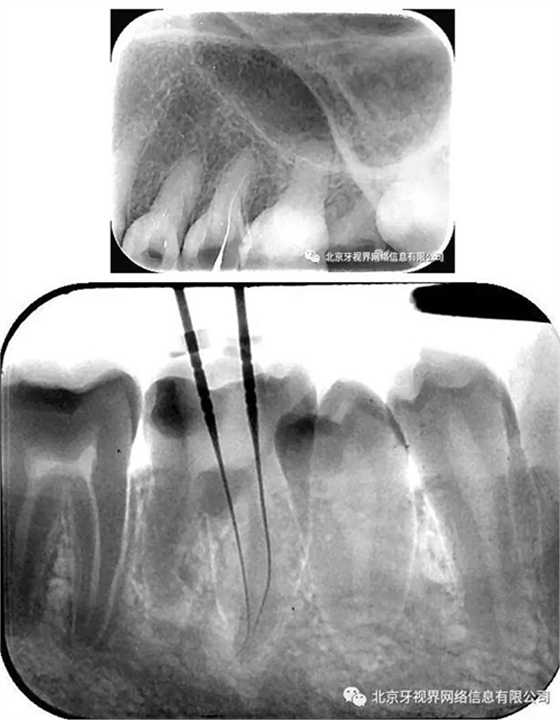

輔助檢查:15根尖周低密度影像,根尖1/3向近中彎曲

(1)15根尖周低密度影像結(jié)合查體診斷根尖周炎,根尖中下段明顯彎曲,能否疏通全長,順利抵達根尖區(qū)為術(shù)者首要考慮。

15備洞,揭頂,10#擴大器預彎后疏通至全長,次氯酸鈉加超聲蕩洗,氫氧化鈣糊劑封藥,玻璃離子暫封,隨診。

4.此例病例中,術(shù)前分析后,采取先解放其中上段后,10#擴大器預彎緩慢前行,抵達根尖區(qū)。